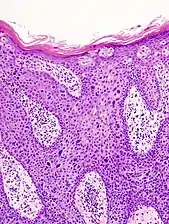

Histopathologically, the epidermis in cSCC in situ (Bowen's disease) will show hyperkeratosis and parakeratosis. There will also be marked acanthosis with elongation and thickening of the rete ridges. These changes will overly keratinocytic cells which are often highly atypical and may in fact have a more unusual appearance than invasive cSCC. The atypia spans the full thickness of the epidermis, with the keratinocytes demonstrating intense mitotic activity, pleomorphism, and greatly enlarged nuclei. They will also show a loss of maturity and polarity, giving the epidermis a disordered or "windblown" appearance.

Two types of multinucleated cells may be seen: the first will present as a multinucleated giant cell, and the second will appear as a dyskeratotic cell engulfed in the cytoplasm of a keratinocyte. Occasionally, cells of the upper epidermis will undergo vacuolization, demonstrating an abundant and strongly eosinophilic cytoplasm. There may be a mild to moderate lymphohistiocytic infiltrate detected in the upper dermis.[12]

- Histopathology of squamous-cell carcinoma in situ (black arrow), compared to normal skin, showing marked atypia.

- Squamous-cell carcinoma in situ, showing prominent dyskeratosis and aberrant mitoses at all levels of the epidermis, along with marked parakeratosis.[12]